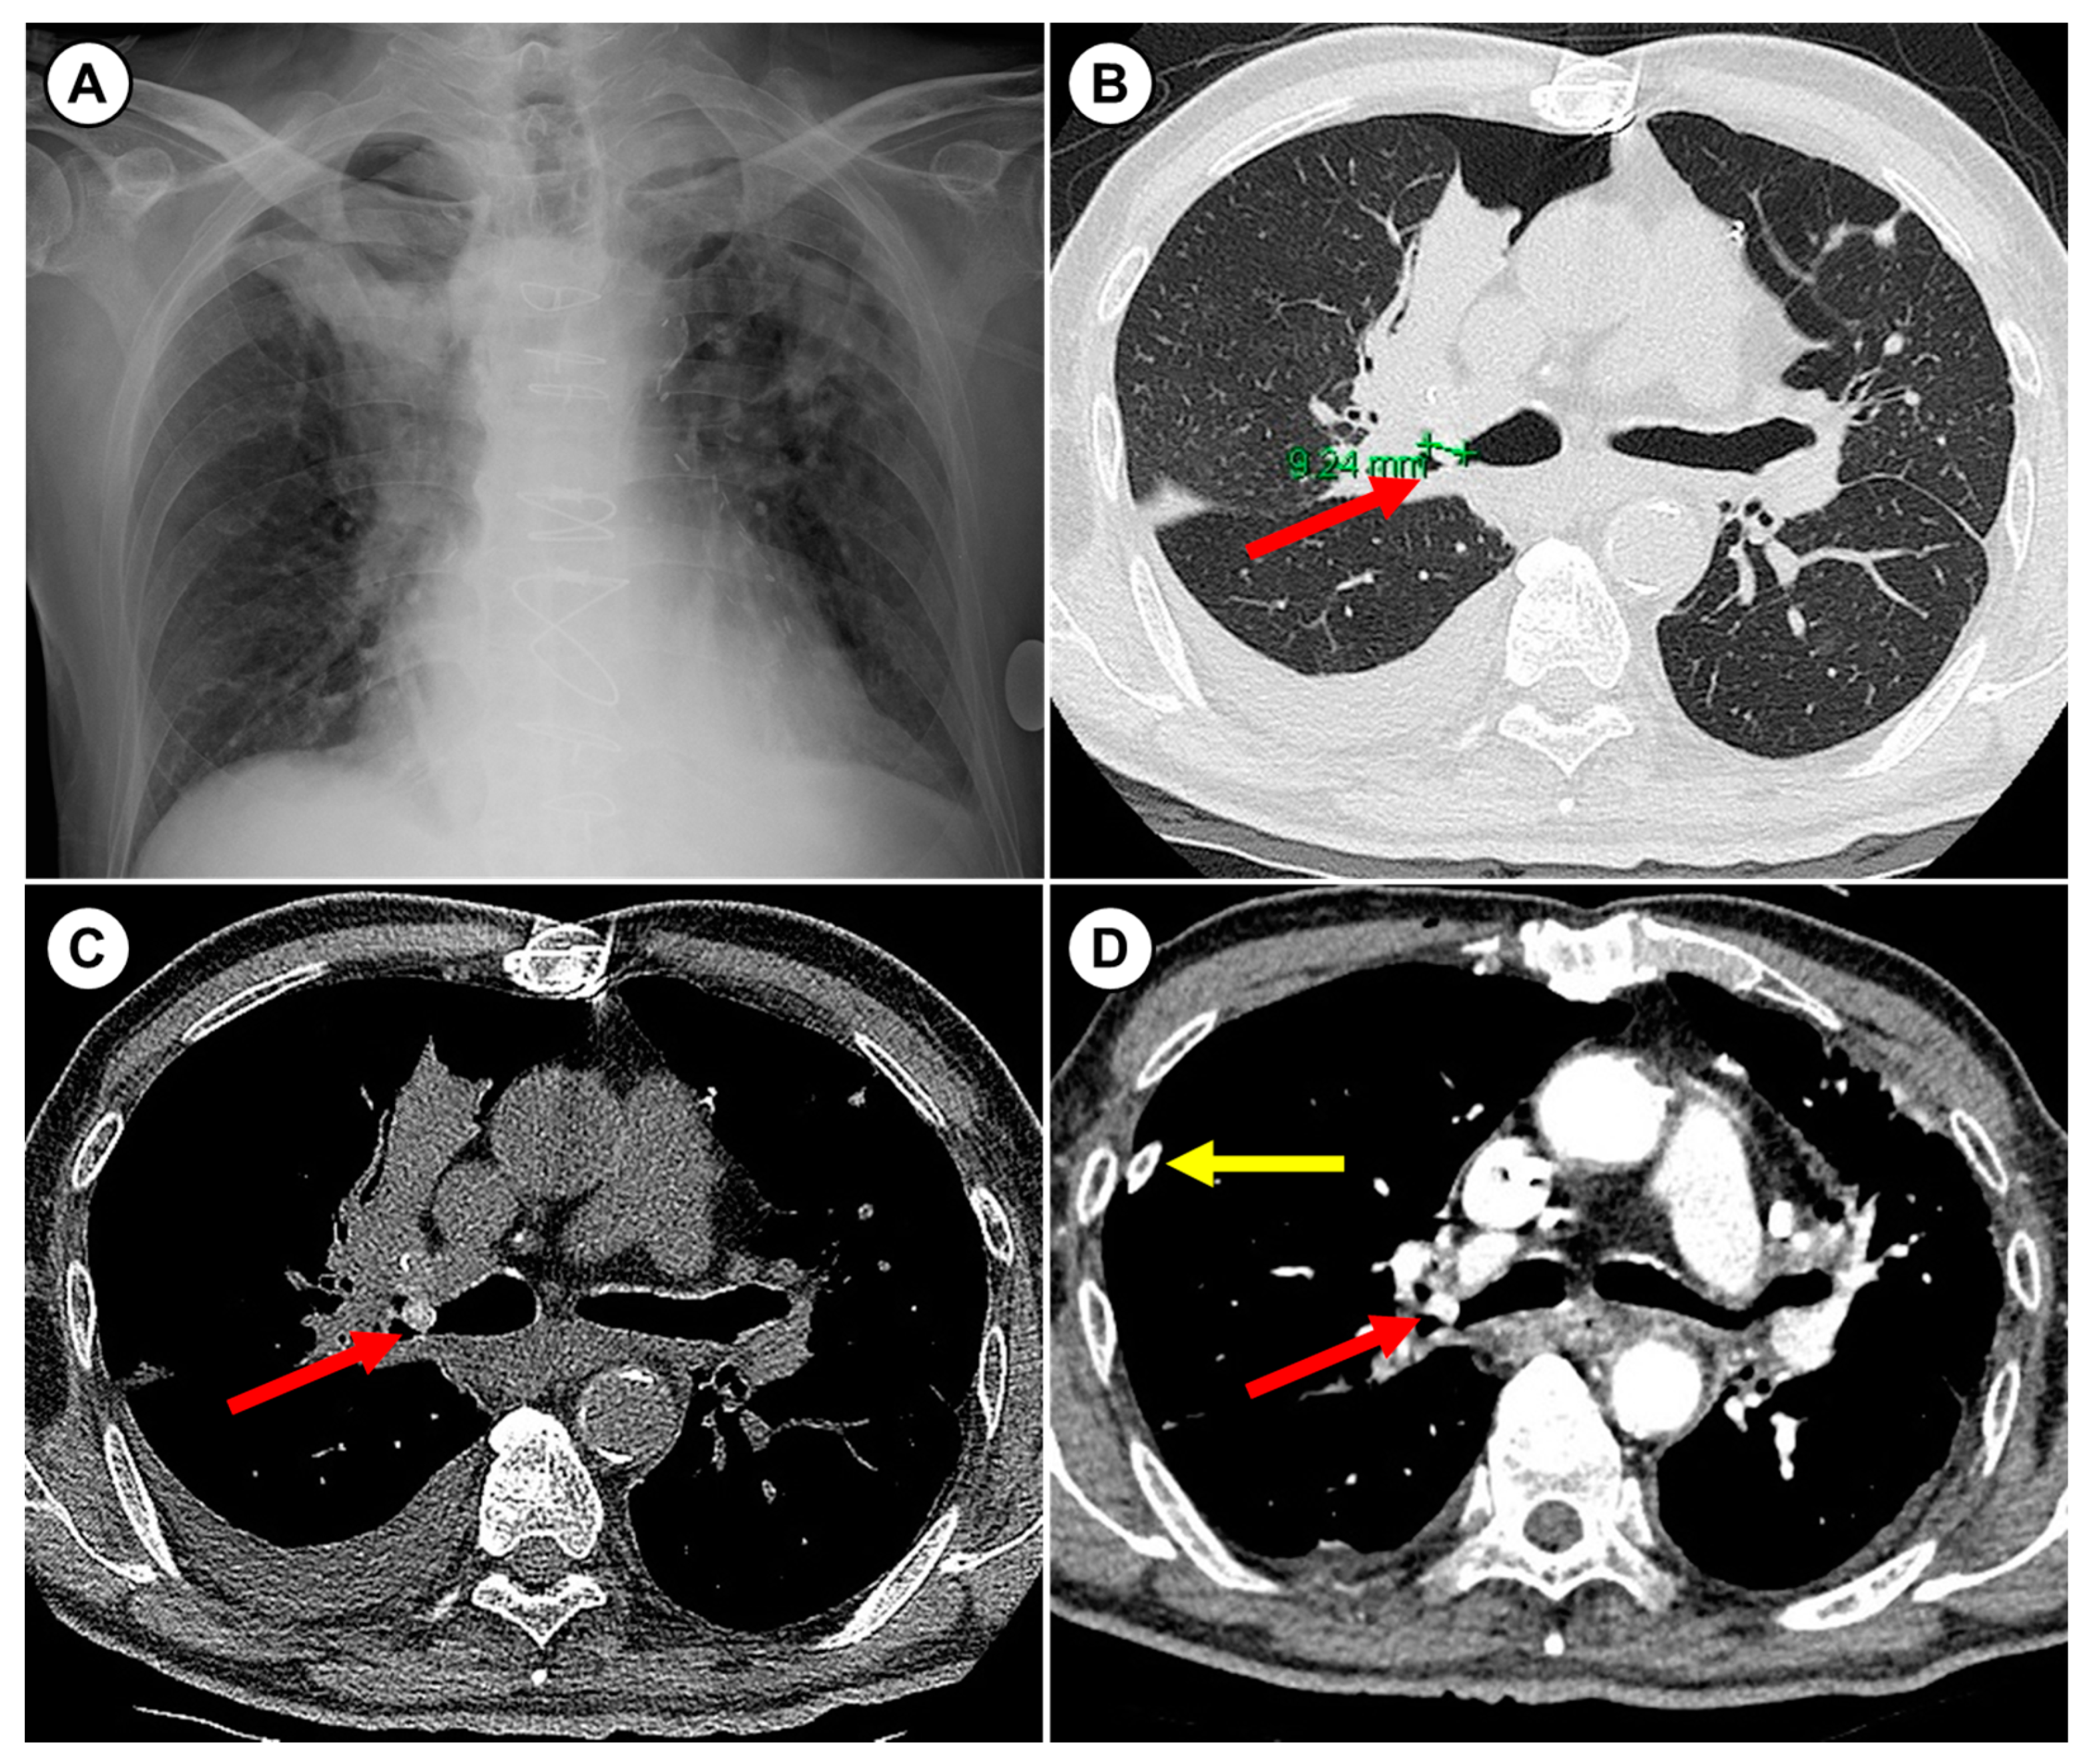

2. Case Presentation